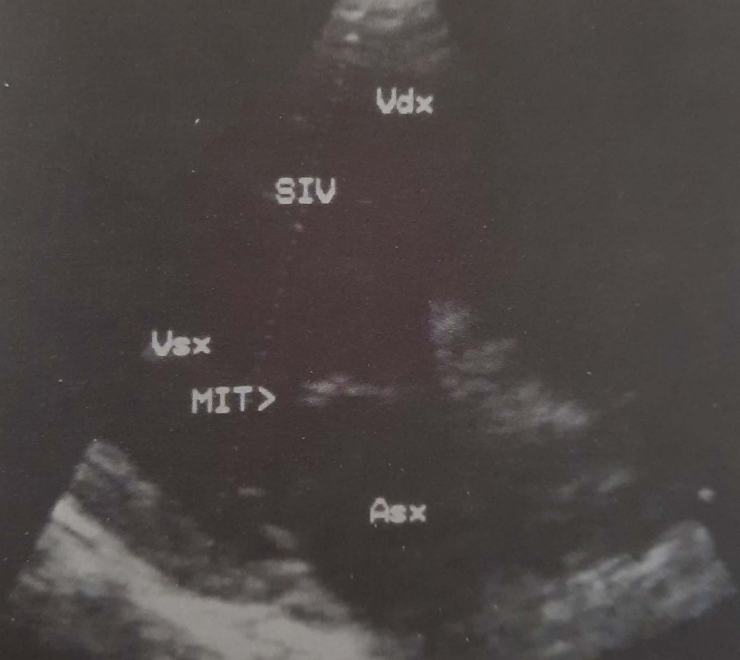

Plani i skanimit korrespondon me aksin gjatësor të organit (djathtas). Baza e zemrës është poshtë djathtas, apex lart majtas. Ky seksion vlerëson ekografinë e valvulës mitrale. Asx = atriumi i majtë; MIT = valvula mitrale; SIV = septum interventrikular; Vdx = ventrikuli i djathtë; Vsx = ventrikuli i majtë.